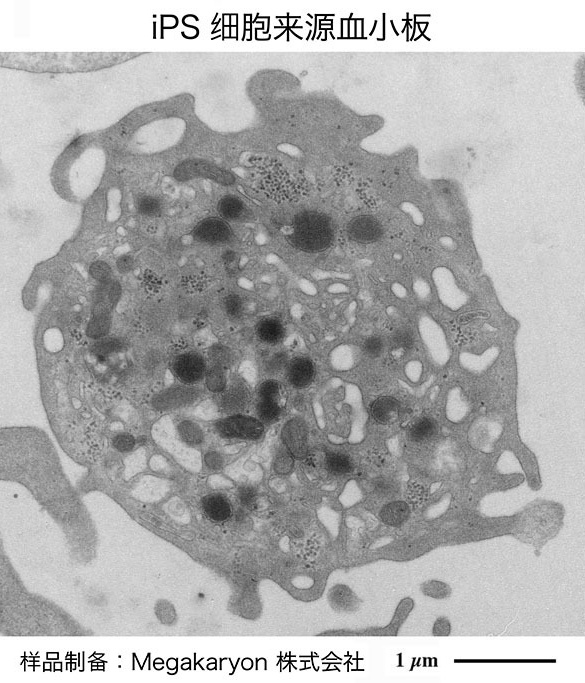

服务于iPS细胞来源血小板制剂开发与临床应用的电子显微镜解析

Electron Microscopical Evaluation of iPS Cell-Derived Human Blood Platelets for Clinical Transfusion

作为京都大学iPS细胞研究所(CiRA)江藤浩之教授实验室、Megakaryon株式会社以及日立高新技术株式会社(Hitachi High-Tech)的产学研合作项目,我们正在开展血小板及其前体细胞巨核细胞的超微形态分析,旨在能够早日实现iPS细胞来源血小板制剂的开发与临床应用。

As an industry-academia collaboration project with Prof. Koji Eto's lab at the Center for iPS Cell Research and Application (CiRA) in Kyoto University, Megakaryon Co., Ltd., and Hitachi High-Tech, Ltd., we are conducting ultra-micromorphological analysis of platelets and their progenitor cells, megakaryocytes, with a view to the early realization of iPS cell-derived platelet products and clinical applications.